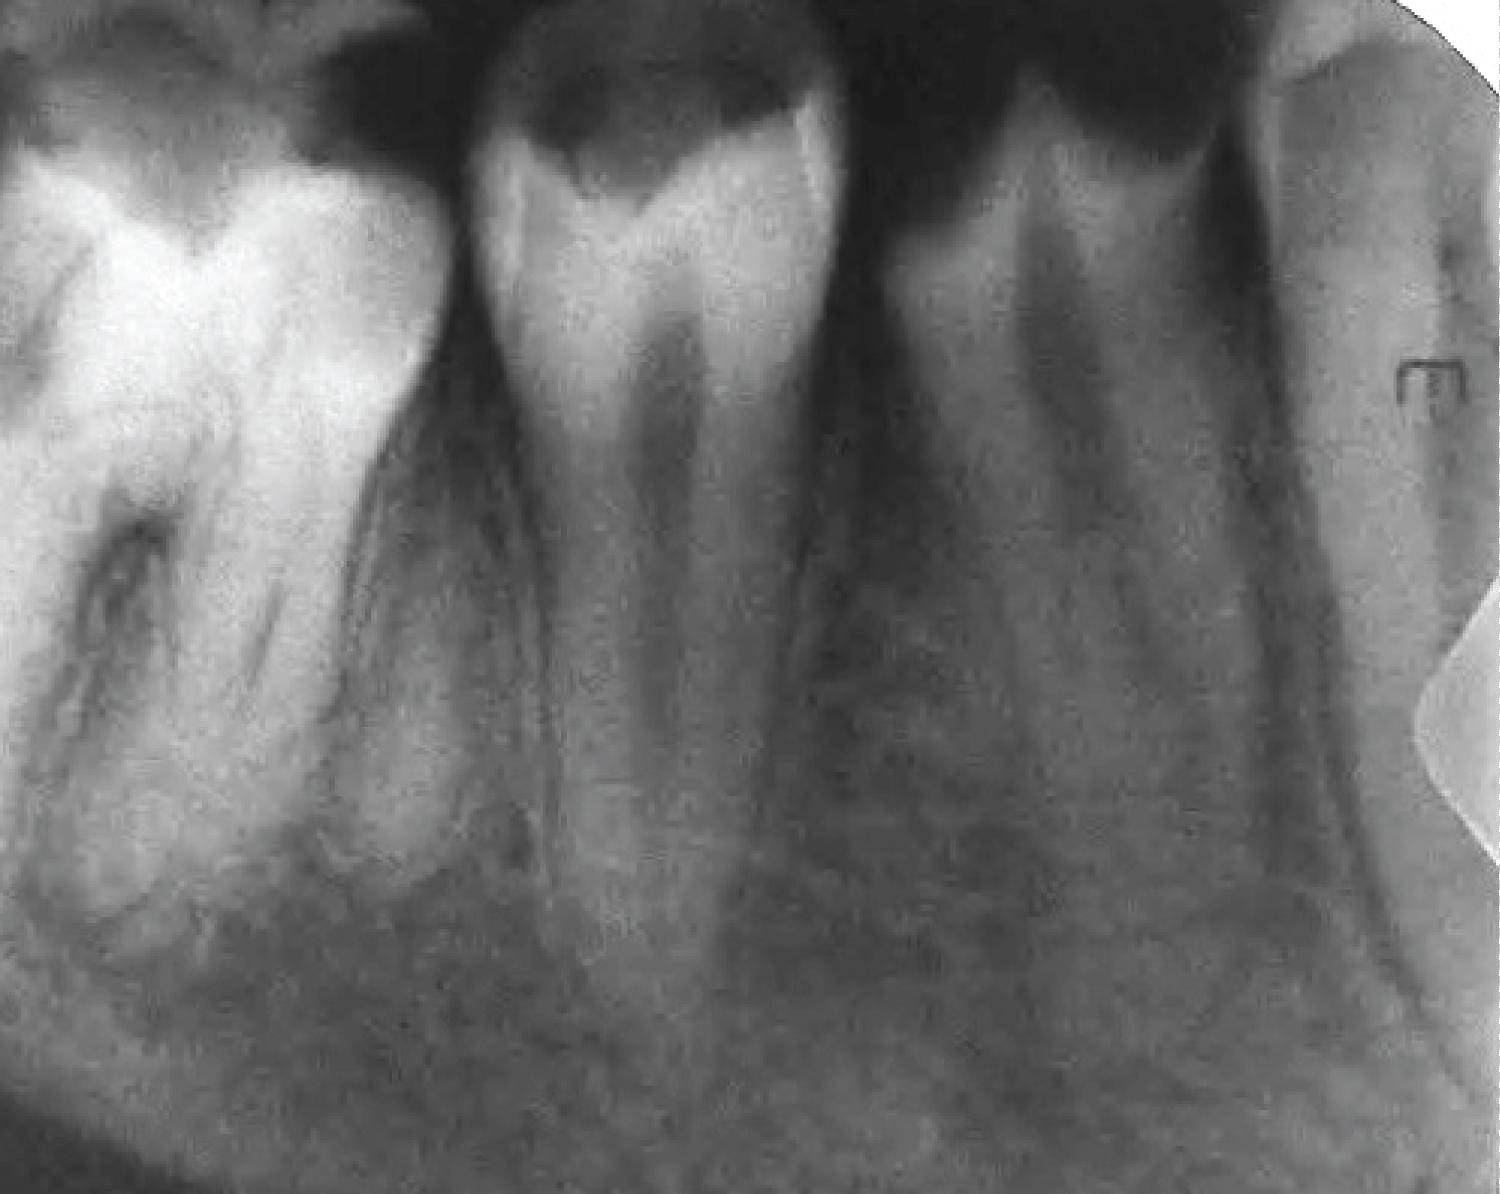

A careful clinical examination revealed a temporary filling, including occlusal and distal surfaces of tooth #35. Tooth #35 was not mobile, and periodontal probing was within physiological limits. Electric pulp testing and cold test were inapplicable, and the tooth was feeling different on percussion. A preoperative radiograph showed radiopaque filling material in the pulp space. It also showed apical radiolucency related to both roots of tooth #35 (Figure 4). Impacted supernumerary premolar was noticed the area between the mesial root of tooth #36 and the distal root of tooth #35. A pulpal diagnosis of previously initiated therapy with asymptomatic apical periodontitis was made. Therefore, a nonsurgical root canal treatment was planned. The treatment plan was discussed with the patient, and the patient signed the consent form.

Figure 4: A preoperative periapical radiograph of tooth #35. View Figure 4

Based on the two-dimensional radiographic images of the two cases reported, the radiographic findings suggested the presence of C-shaped mandibular premolars. Cone-beam computed tomography (CBCT) is a useful image to confirm a C-shaped root canal system [19,20]. CBCT images provide three-dimensional imaging that enables the operator to study the anatomical structures and the pathological changes with more precise details. However, in this case, CBCT images were not taken because it was not available in the Albaha region at the time of treatment. Furthermore, the canals orifices orientations indicate C-shaped canal, as shown in Figure 5.

A sudden narrowing of the root canal space known as “the fast break phenomena” indicates its division into two or more canals [2,15]. This was evident in both cases preoperative radiographs. Pulp chamber map analysis with the aids of the magnifying loupes helps in locating all the root canals.